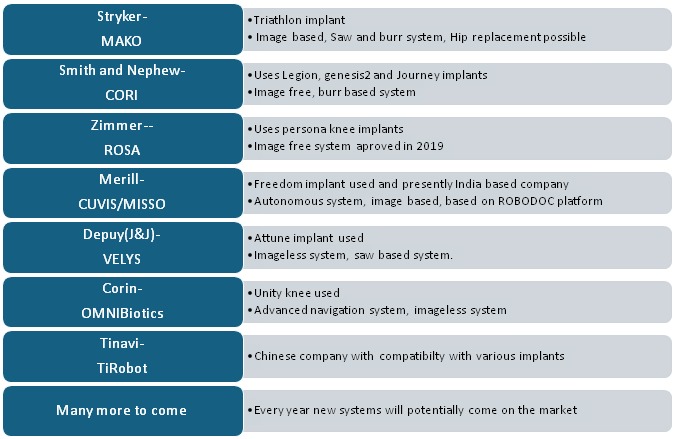

The robotic platform available widely in the world and India has been mentioned in the table below. This is a rapidly evolving subject, and many more platforms are going to be developed in the world of knee replacement surgery. The table below summarizes the implant and the manufacturing companies presently around the world in total knee arthroplasty.